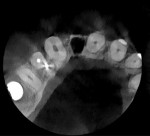

Three months prior to this emergency visit for the maxillary right lateral incisor, the patient had been treated in the practice with an implant in the posterior left maxilla and a CBCT scan was acquired. Examination of a cross section of this CBCT scan at the tooth No. 7 position revealed a thin facial plate of bone with dehiscence (Figure 3). As a result, traditional extraction of the lateral incisor and implant placement would require flap exposure of the facial aspect of the ridge and osseous grafting to ensure that the entire implant would be encased in bone following healing. This approach would also negate the possibility of immediately loading the implant and require the patient to wear a removable provisional to replace the missing tooth during healing.